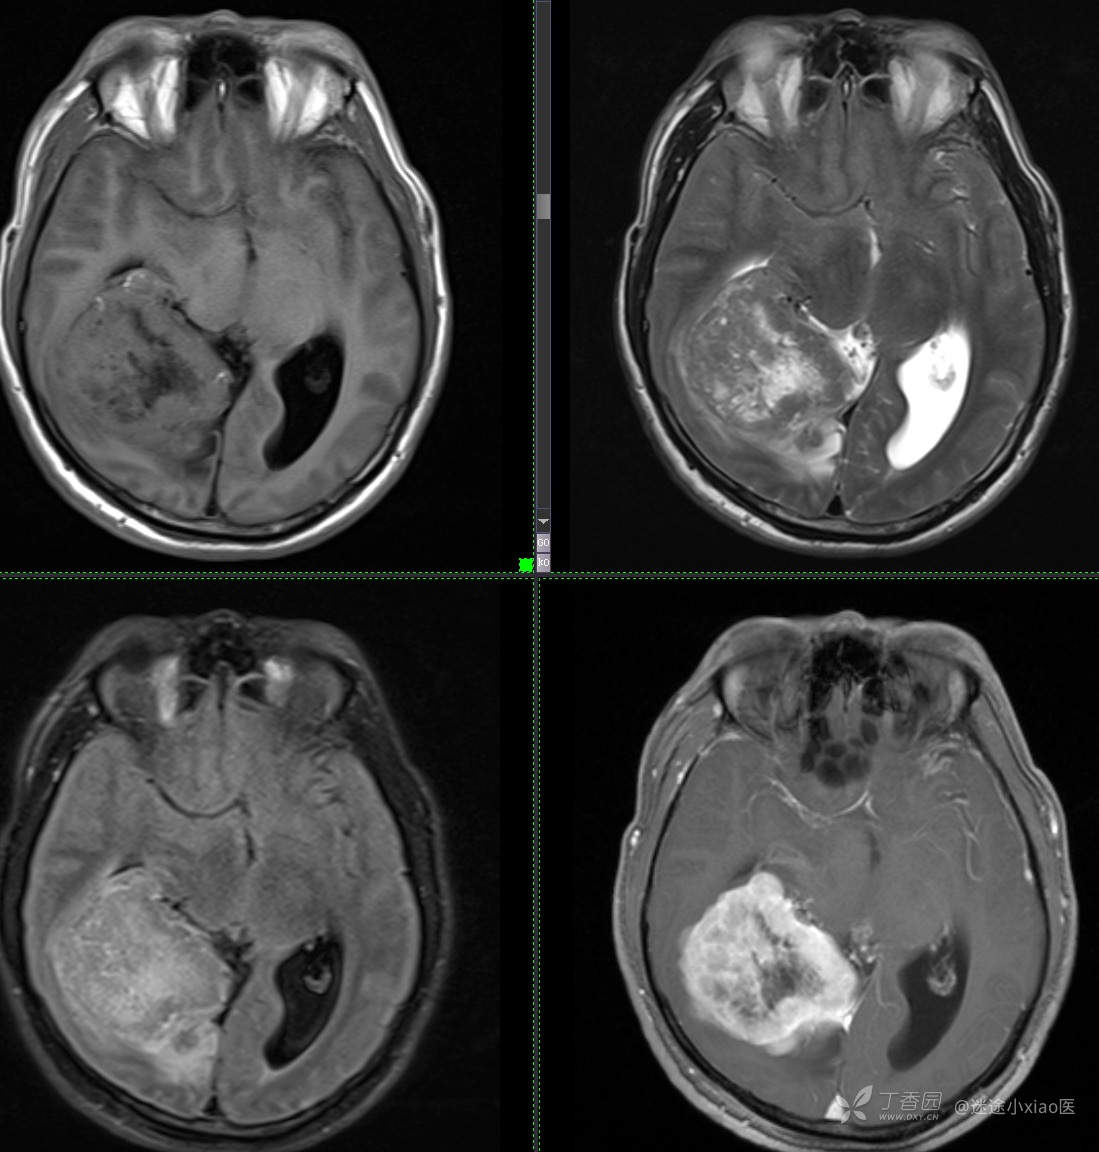

患者年龄:43

患者性别:男

简要病史:头痛3月余,查体无殊